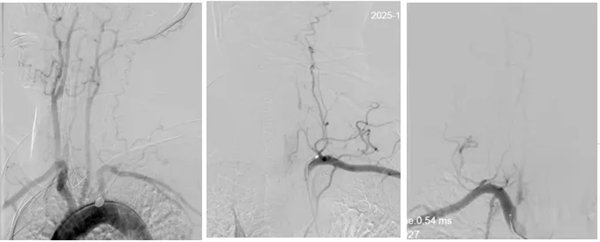

为最大程度抢救脑细胞,缩短脑组织供血恢复间隔,神经内三科卒中救治团队立即启动绿色通道实施介入取栓治疗,麻醉医师迅速抵达导管室,神经内三科主任席聪对患者进行急诊血管造影后发现:患者左椎动脉起始段闭塞,右椎动脉起始部次全闭塞。

术中,介入团队精准定位血管闭塞部位,通过微导丝“探路”联合球囊扩张技术开通右侧椎动脉开口,造影椎开口残余狭窄60%。基底动脉血栓形成,基底动脉管腔狭窄55%,基底动脉尖堵塞,右侧大脑后动脉及小脑上动脉未见显影,左侧大脑后动脉P3以远闭塞。

席聪准确锁定患者基底动脉处血栓,采用抽吸取栓技术快速开通血管,成功取出堵塞部位2cm的血栓。再次造影示:右侧大脑后及双侧小脑上动脉再通,右侧大脑后动脉P3段以远闭塞,考虑慢性闭塞,推注替罗非班,血流明显加快。随后采用支架植入术开通右侧椎动脉开口处,术中影像显示:支架贴壁良好,无明显残余狭窄,颅内血管显影良好。